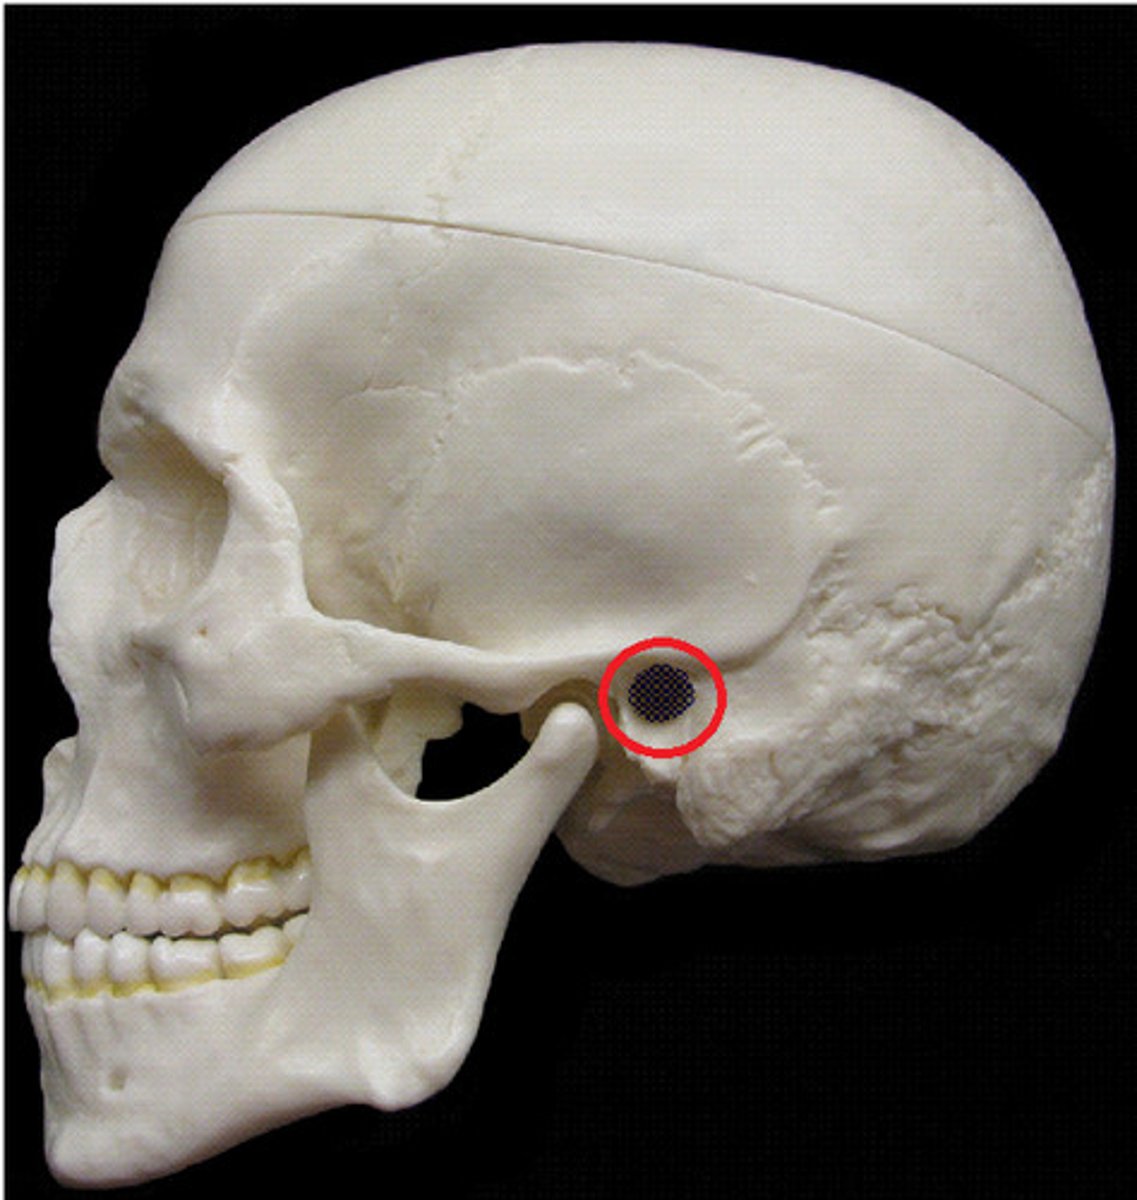

pterion

Junction of frontal, parietal, sphenoid, and temporal bones. Structural vulnerability as it is thin and middle meningeal artery is just deep, so hard head blow can result in subdural hematoma